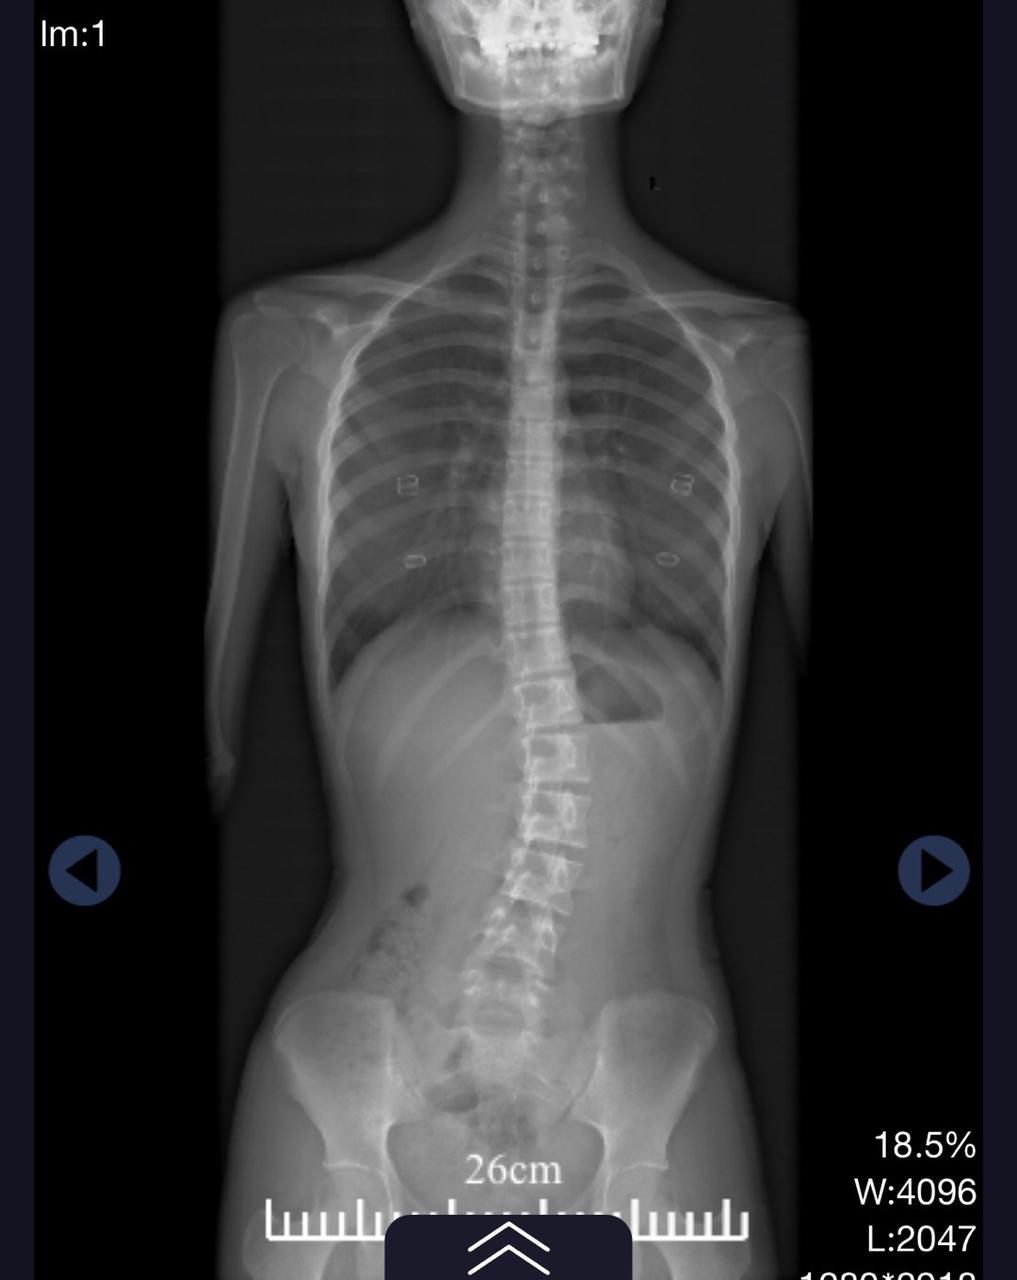

患者小谢,女,13岁,4个月前在学校体检时发现体态异常,遂至康复中心就诊,拟行康复治疗;既往体健。无脊柱异常家族史、无脊柱外伤史、无脊柱手术史。